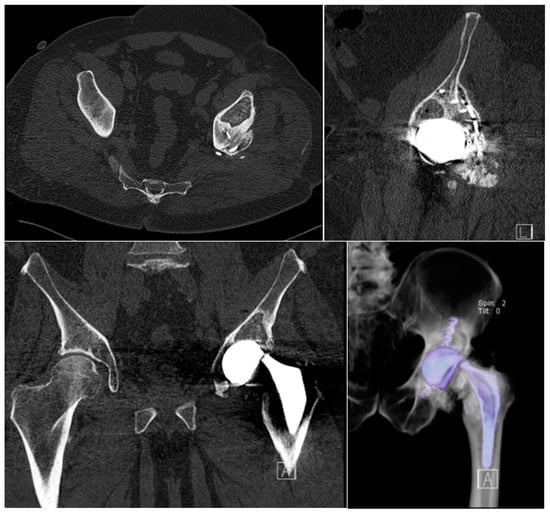

2. Case Presentation

3.1. Intraoperative Findings